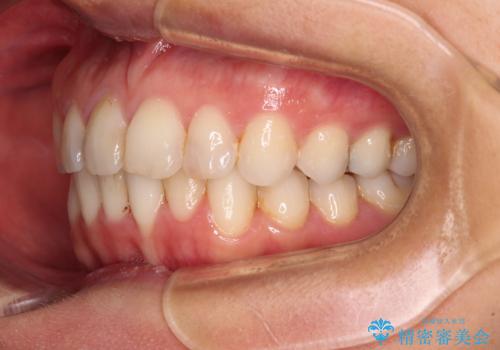

前歯の叢生をいつの間にか改善 インビザラインによる矯正治療

- 前歯のデコボコを気にして来院された患者様です。

IPR(歯と歯の間を削る)によってデコボコが解消するように設計し、インビザラインにより治療を行うこととしました。

下顎善の叢生をもう少し改善したかったのですが、患者様は十分に整ったとのことで治療を終えることになりました。